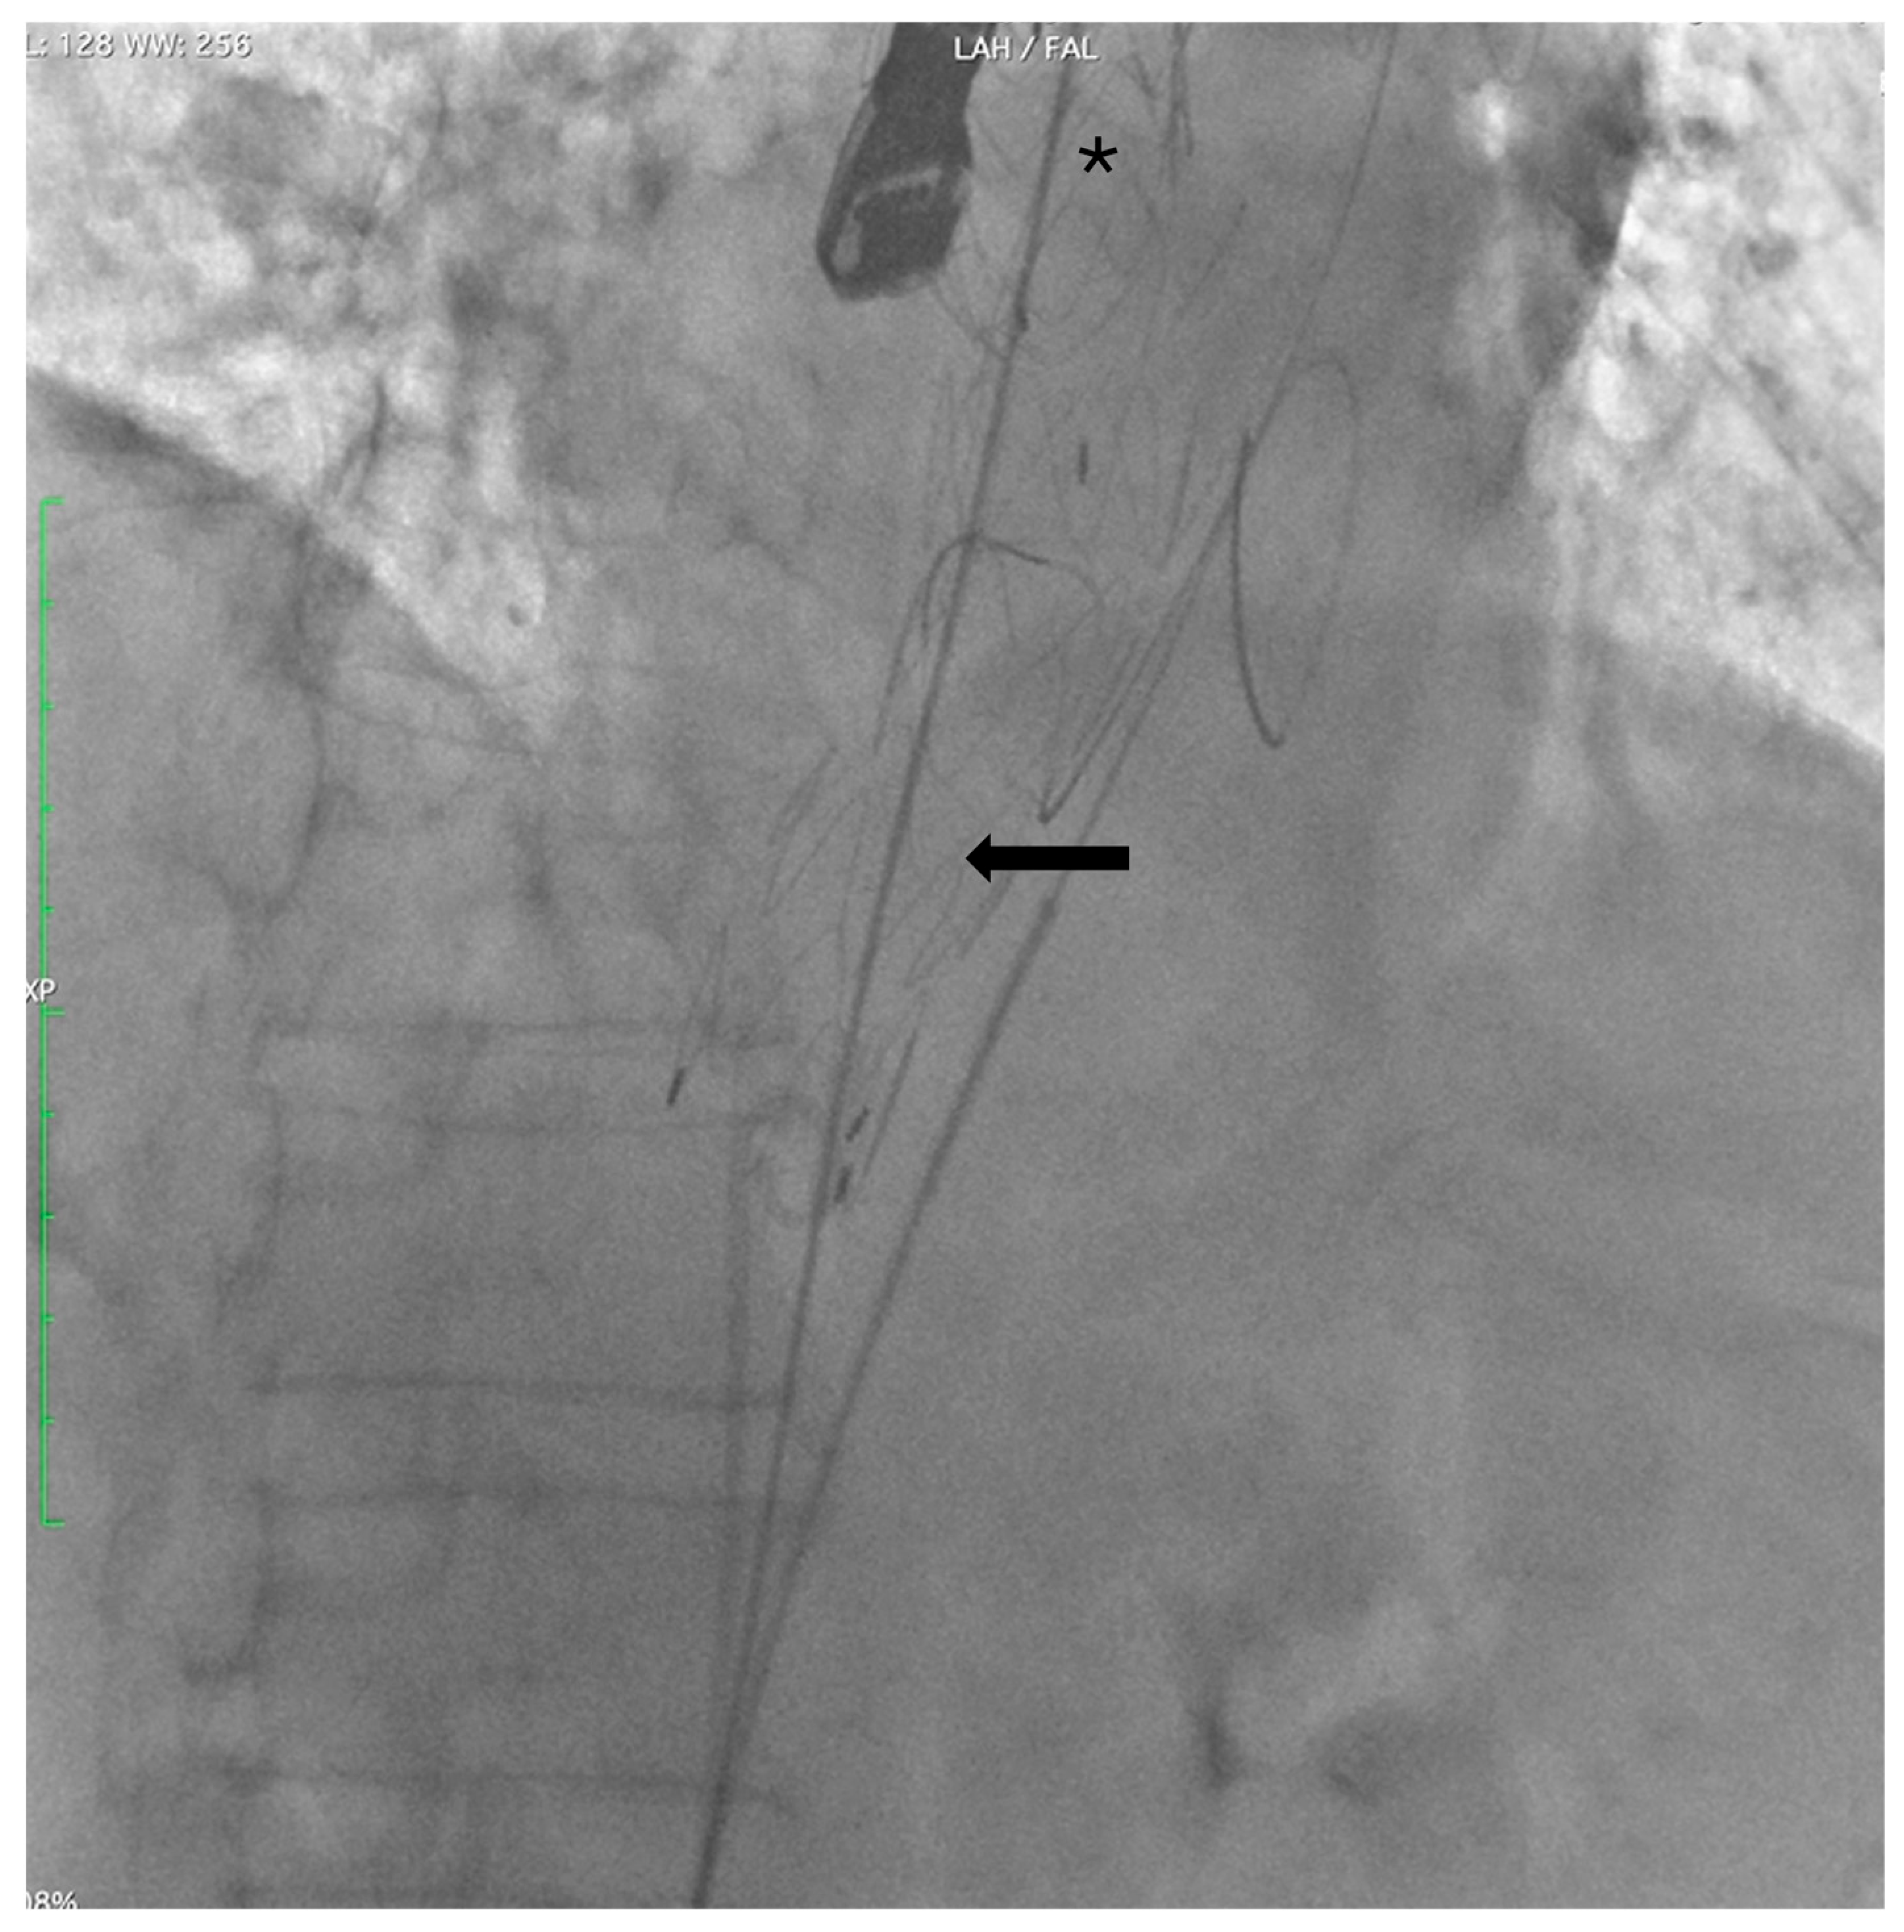

Two extra-stiff guidewires were positioned: one via the RCFA into the true lumen (TL), and the other via the LCFA into the FL. A Terumo Aortic endograft (36–32–199 mm) was deployed over the RCFA guidewire with partial overlap of the existing stent graft, successfully sealing the distal re-entry tears. (Figure 3).

Figure 3. Angiographic control after deployment of a Terumo Aortic endograft (arrow) into the true lumen, partially overlapping the prior TEVAR (*).